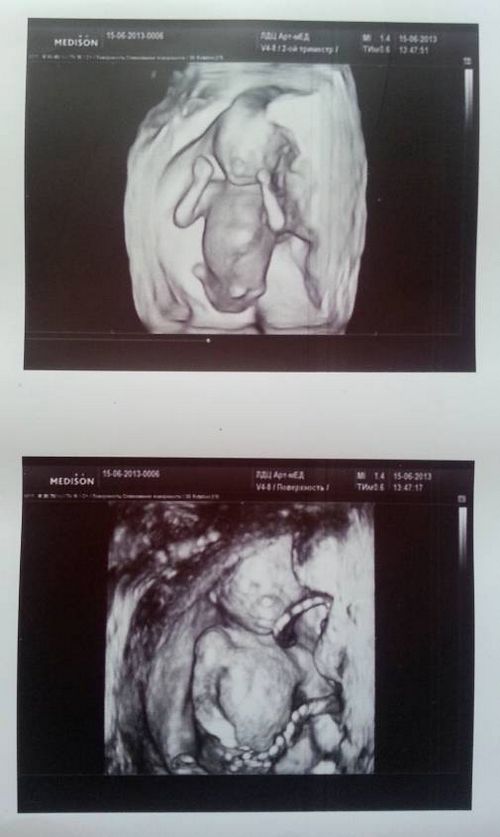

Знімки УЗД на 16 тижні

Розмір плоду на 16 тижні вагітності у вазі становить 100-120 г, а в зростанні від куприка до тім'ячка - 11 см. Малятко вже тримає прямо шийку, він навчився повертати головку в сторону. Посилено працює сердечко малюка, а печінку почала виконувати і травну функцію. Нирки і сечовий міхур теж включилися в активну роботу. Пісяє ваш малюк кожні 45 хвилин.